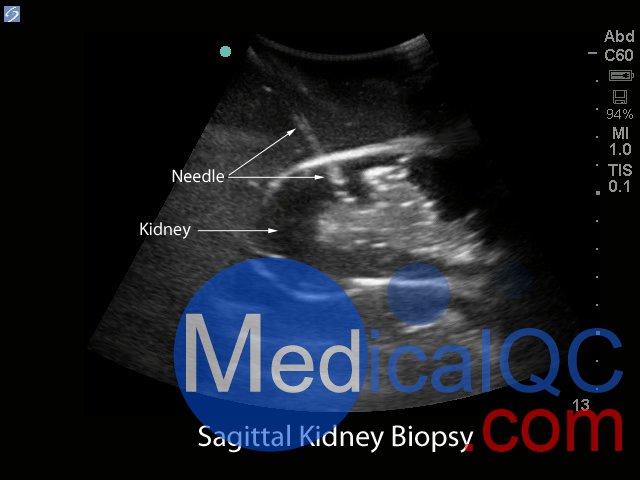

Blue Phantom的經(jīng)皮腎穿刺活檢超聲訓(xùn)練模型允許使用芯針穿刺活檢或穿刺穿刺技術(shù)重復(fù)進(jìn)行針頭活檢。該模型提供了解剖學(xué)上正確的成年男性軀干,其超聲組織模塊包含皮膚,肋骨和右腎以及周圍組織。腎臟的內(nèi)部和外部結(jié)構(gòu)在其逼真度和成像特性方面極佳,并且包含腎皮質(zhì),腎髓質(zhì)以及主要和次要的花萼。使用與真實(shí)人體組織的聲學(xué)特征相匹配的Blue Phantom模擬組織構(gòu)造而成,因此,當(dāng)您在我們的訓(xùn)練模型上使用超聲系統(tǒng)時(shí),您將獲得與在臨床環(huán)境中對患者進(jìn)行成像所期望的相同質(zhì)量。

核心針穿刺活檢程序。使用超聲引導(dǎo)的腎臟活檢模型進(jìn)行核心針頭活檢的臨床醫(yī)生期望從模型中去除組織樣本。取出核心組織樣本后,腎臟中會(huì)留有一個(gè)空氣,其大小相當(dāng)于核心樣本的大小。用戶可以期望在腎臟需要更換之前將核心活檢樣本取出30次(腎臟很容易取出,這樣未使用的上腎臟可以旋轉(zhuǎn)到下極位置)。

針抽吸程序。使用超聲引導(dǎo)的腎臟活檢模型進(jìn)行針抽吸手術(shù)的臨床醫(yī)生可以期望在使用18 – 21號針頭時(shí)具有巨大的實(shí)用性。Blue Phantom的專利自修復(fù)超耐用薄紙可重復(fù)使用。當(dāng)用戶使用鋒利,彎曲的針頭時(shí),將獲得最佳的愈合效果。

超聲成像和程序技能包括;使用超聲系統(tǒng)控制,換能器定位和移動(dòng),識(shí)別腎解剖結(jié)構(gòu),在腎活檢期間避免肋骨出現(xiàn),避免肋骨出現(xiàn),使用超聲將目標(biāo)對準(zhǔn)腎活檢的適當(dāng)位置并執(zhí)行超聲引導(dǎo)的腎活檢程序。使用配置了適當(dāng)?shù)哪I臟活檢換能器的任何超聲成像系統(tǒng),此超聲動(dòng)手訓(xùn)練模型將表現(xiàn)良好。這種超聲體模模型非常適合包括腎臟科,介入放射學(xué),外科手術(shù),外科手術(shù)訓(xùn)練計(jì)劃,超聲訓(xùn)練計(jì)劃,模擬中心,外科技能中心,醫(yī)學(xué)教育設(shè)施,腎臟活檢設(shè)備制造商和超聲制造商進(jìn)行超聲教育和演示的專業(yè)。